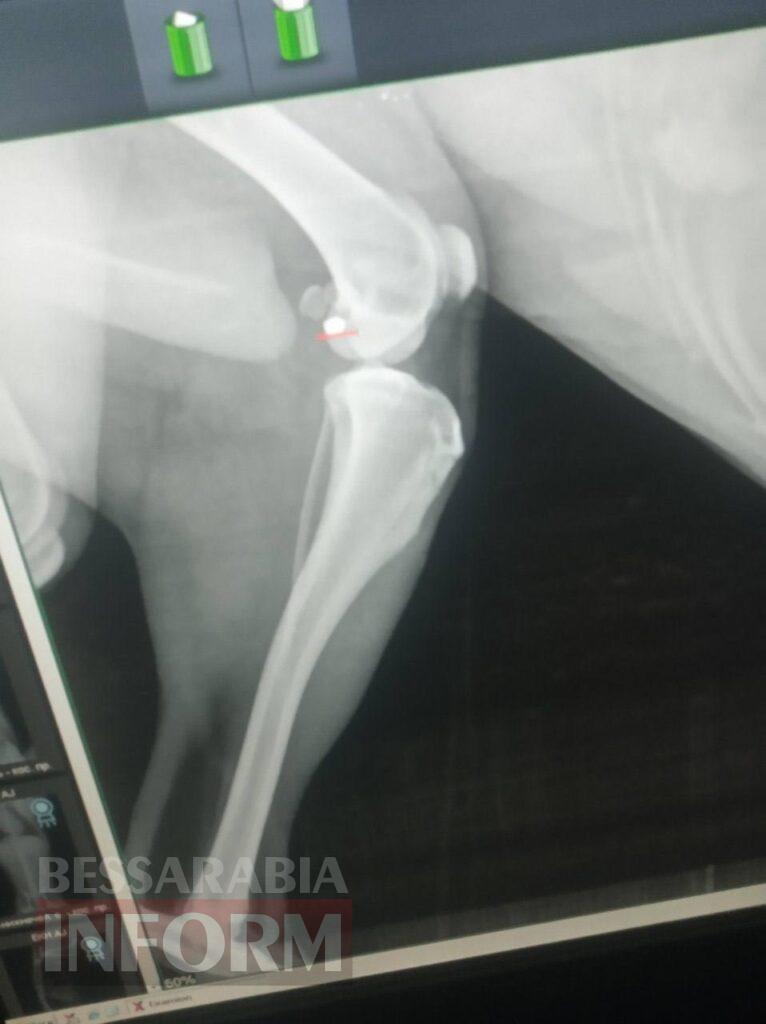

У Білгороді-Дністровському зафіксували черговий випадок поранення безпритульного собаки із пневматичної зброї. Чотирилапого доставили до місцевої ветклініки із симптомами отруєння, а на рентгені лікар виявив кулю. На жаль, цей інцидент за останні роки — вже не перший. Про ситуацію «Бессарабії INFORM» розповіла місцева жителька Вероніка Кухарська.

За словами Вероніки, яка згодом забрала до себе собаку на перетримку, у тварини було отруєння — її у важкому стані на вулиці помітили діти. Однак під час огляду ветеринар виявив ще й поранення. Як розповіла нам жінка, маленьку чотирилапу оперувати не стали — куля так і залишиться в її тілі через відсутність потреби у видаленні:

«Її діти принесли — кажуть, собачка помирає. Ми її одразу повели до ветеринарки. У неї було отруєння. Потім намацали ранку в боці, і нас направили на рентген. Зробили рентген — сказали, що в неї стріляли з пневматичної зброї. Стріляли плюс-мінус півтора тижня тому», — розповіла жінка.

Рентген першого собаки, у якого стріляли у 2023 році. Фото виданню надала пані Вероніка